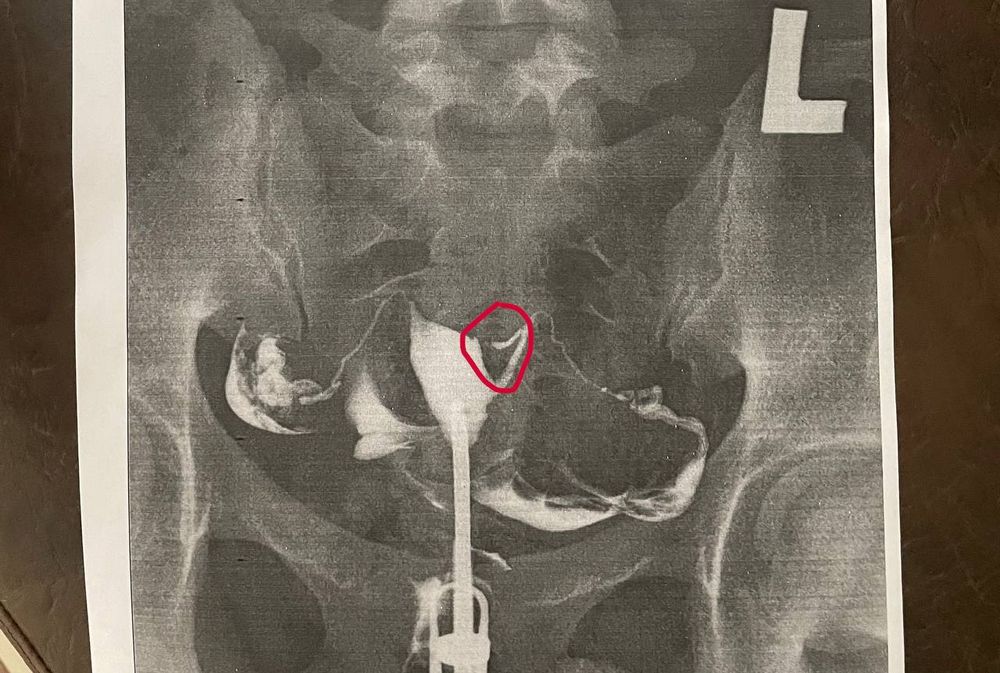

Что это может быть ?

Девочки всем привет !) Скажите пожалуйста может кто-то сталкивался с таким ? Понимаю ,что очень на врд ли ,но может быть было ) Вчера делала ГСГ и увидели ,что в данной части нет жидкости ,почему такое может быть ? Может полип какой-то ? Но ни на одном узи мне про них ничего не говорили (